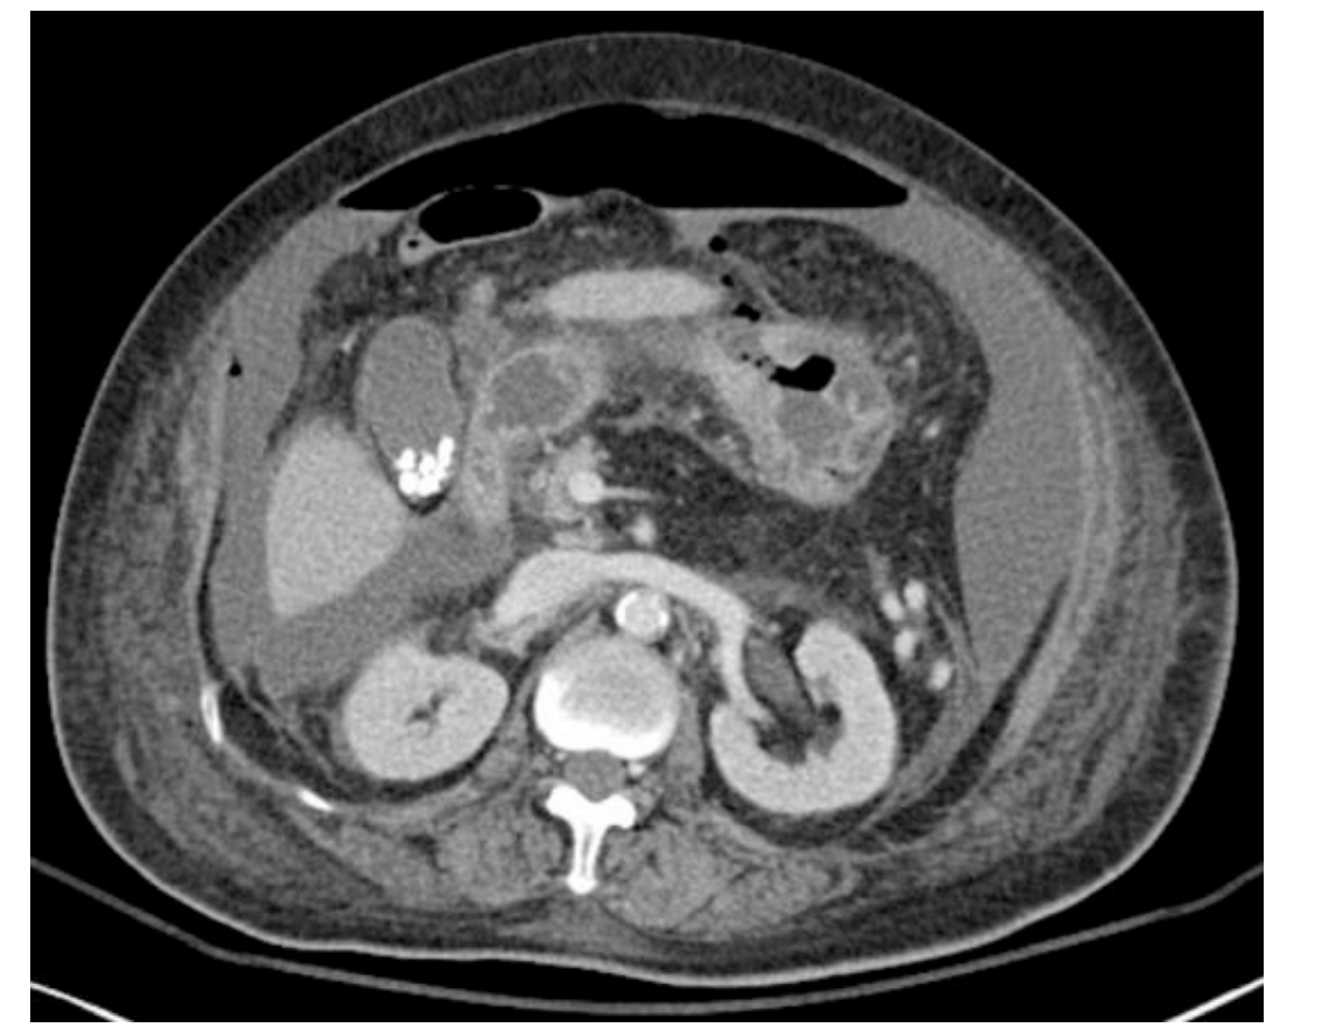

what CT featues of pancreatitis are associated with severe disease?

focal or diffuse enlargement

fat stranding

single or multiple fluid collections

necrosis